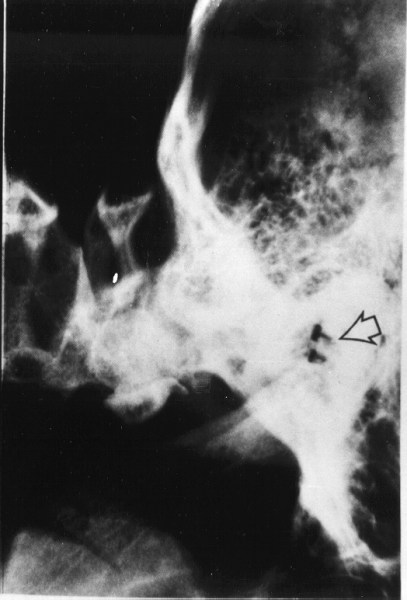

16th November 1998 Metal Electrodes verified by Graeme Marlow Macdonald, MB BS, Neurosurgeon, Auckland Hospital, New Zealand, as being embedded deep within the ear sockets under the temporal plates. |

January 1999 Digital Enhancement: Closeup view of reflecting metal electrode. |

CT scan of the mid 1990s showing definite presence of two metal plates above the eye sockets. What look like two "radio knobs" protrude from each plate.